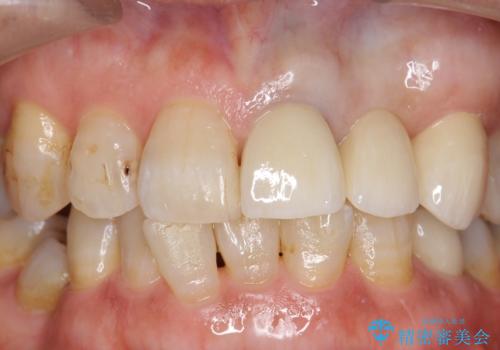

オールセラミッククラウン 前歯のブリッジ 気になる見た目の改善

- 左側の前歯の見た目が気になるといらっしゃった方の症例です。

左上1、2番目の歯は仮歯の状態だったので外して状態を確認したところ、左上2は垂直的な歯根破折を認めたため抜歯となりました。左上1は再根管治療を行いました。

左上2抜歯後、骨および歯肉の回復を待ち、オールセラミッククラウンのブリッジによる欠損補綴を行いました。